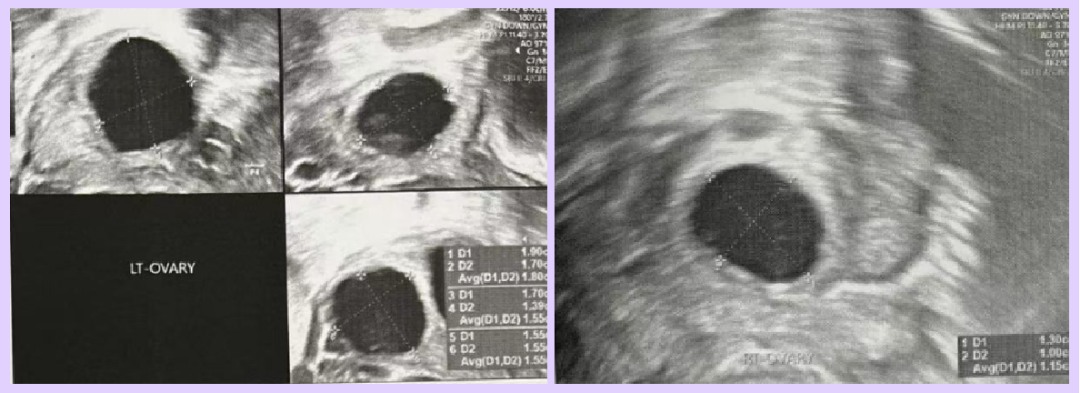

Both partners are of advanced reproductive age and had previously attempted IVF twice without success. After evaluation, the doctor diagnosed the female patient with diminished ovarian reserve (DOR) due to her age. Ultrasound revealed only 3 usable follicles (diameter > 4mm), indicating a significantly reduced ovarian reserve.

- Day 5 of Stimulation (Thailand)

- Ultrasound Findings:

- Right ovary: 1 follicle (10mm)

- Left ovary: 3 follicles (14mm, 11mm, 10mm)

- Day 7 of Stimulation (Thailand)

- Ultrasound Findings:

- Right ovary: 1 follicle (11mm)

- Left ovary: 3 follicles (18mm, 15mm, 15mm)

- Day 9 of Stimulation (Thailand)

- Ultrasound Findings:

- Right ovary: 1 follicle (16mm)

- Left ovary: 3 follicles (23mm, 20mm, 18mm)

- Day 17 of Menstrual Cycle (Thailand)

- Ultrasound Findings: Endometrial thickness 11 mm